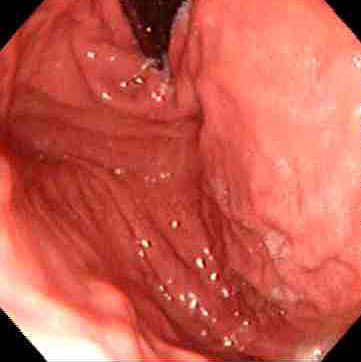

![]() | The esophagus is at the left. The stomach has been opened along the greater curvature to reveal a normal fundus. In the fundus can be seen the lesser curvature. Just beyond the antrum is the pylorus emptying into the first portion of duodenum is at the lower right. The normal appearance of the gastric fundus on upper GI endoscopy is shown below at the left, with the normal duodenal appearance at the right. |